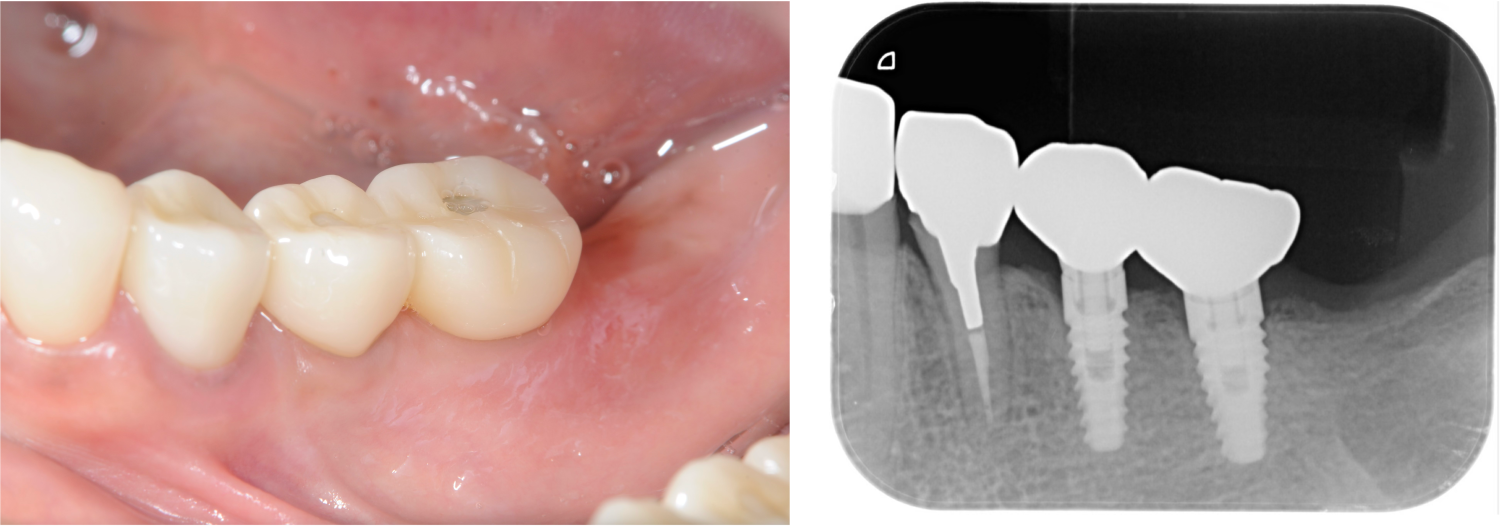

下顎臼歯部が欠損した患者さんのインプラント治療の症例②(うえだ歯科)

| 主訴 | 全顎治療希望、下の奥の歯が無いので全く噛めない。綺麗で噛めるようになりたい |

| 治療内容 | 下顎臼歯部欠損放置のため、臼歯部においてスペースがないため、全顎治療を行い咬合再構成を行う。 早期においてインプラント治療、咬合関係を模索した後、全顎にわたりセラミックによる補綴治療、その後メインテナンスに移行 |

| 治療費 | 5,410,000円(税込)(インプラントすべて含む) |

| 治療期間 | 1年8ヶ月 |

| 治療回数 | 80回 |

| 想定されたリスク | 食いしばり(パラファンクション)によるセラミックの破折、歯の破折 |